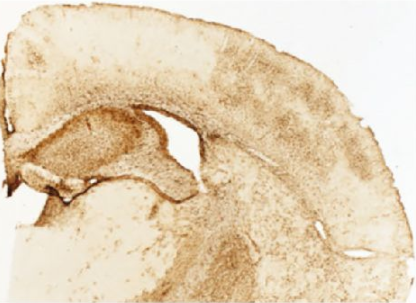

圖:自由漂浮Bcs1lc.232A>Gmouse腦皮質(zhì)冷凍切片用抗GFAP染色,然后二次試劑DAB,并安裝在明膠載玻片上(SB目錄號(hào)SLD01)。圖片來(lái)自Tegelberg S、Toma?id N、Kallj?rvi J、Purhonen

J、 埃爾默